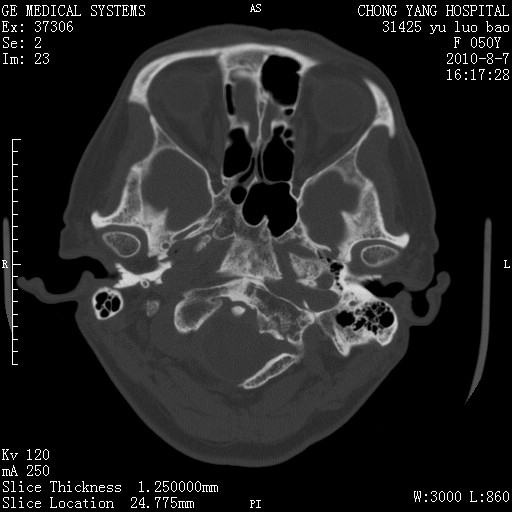

骨窗示右侧内听道扩大,考虑右侧听神经瘤。

右侧桥小脑角去等密度占位,右侧内听道扩大、骨质吸收,考虑:右侧听神经瘤,建议增强检查。

右侧内听道扩大、骨质吸收,中脑受压左移,考虑:右侧听神经瘤,建议增强检查。支持!

右侧桥小脑角区等密度占位,内耳道扩大,听神经瘤